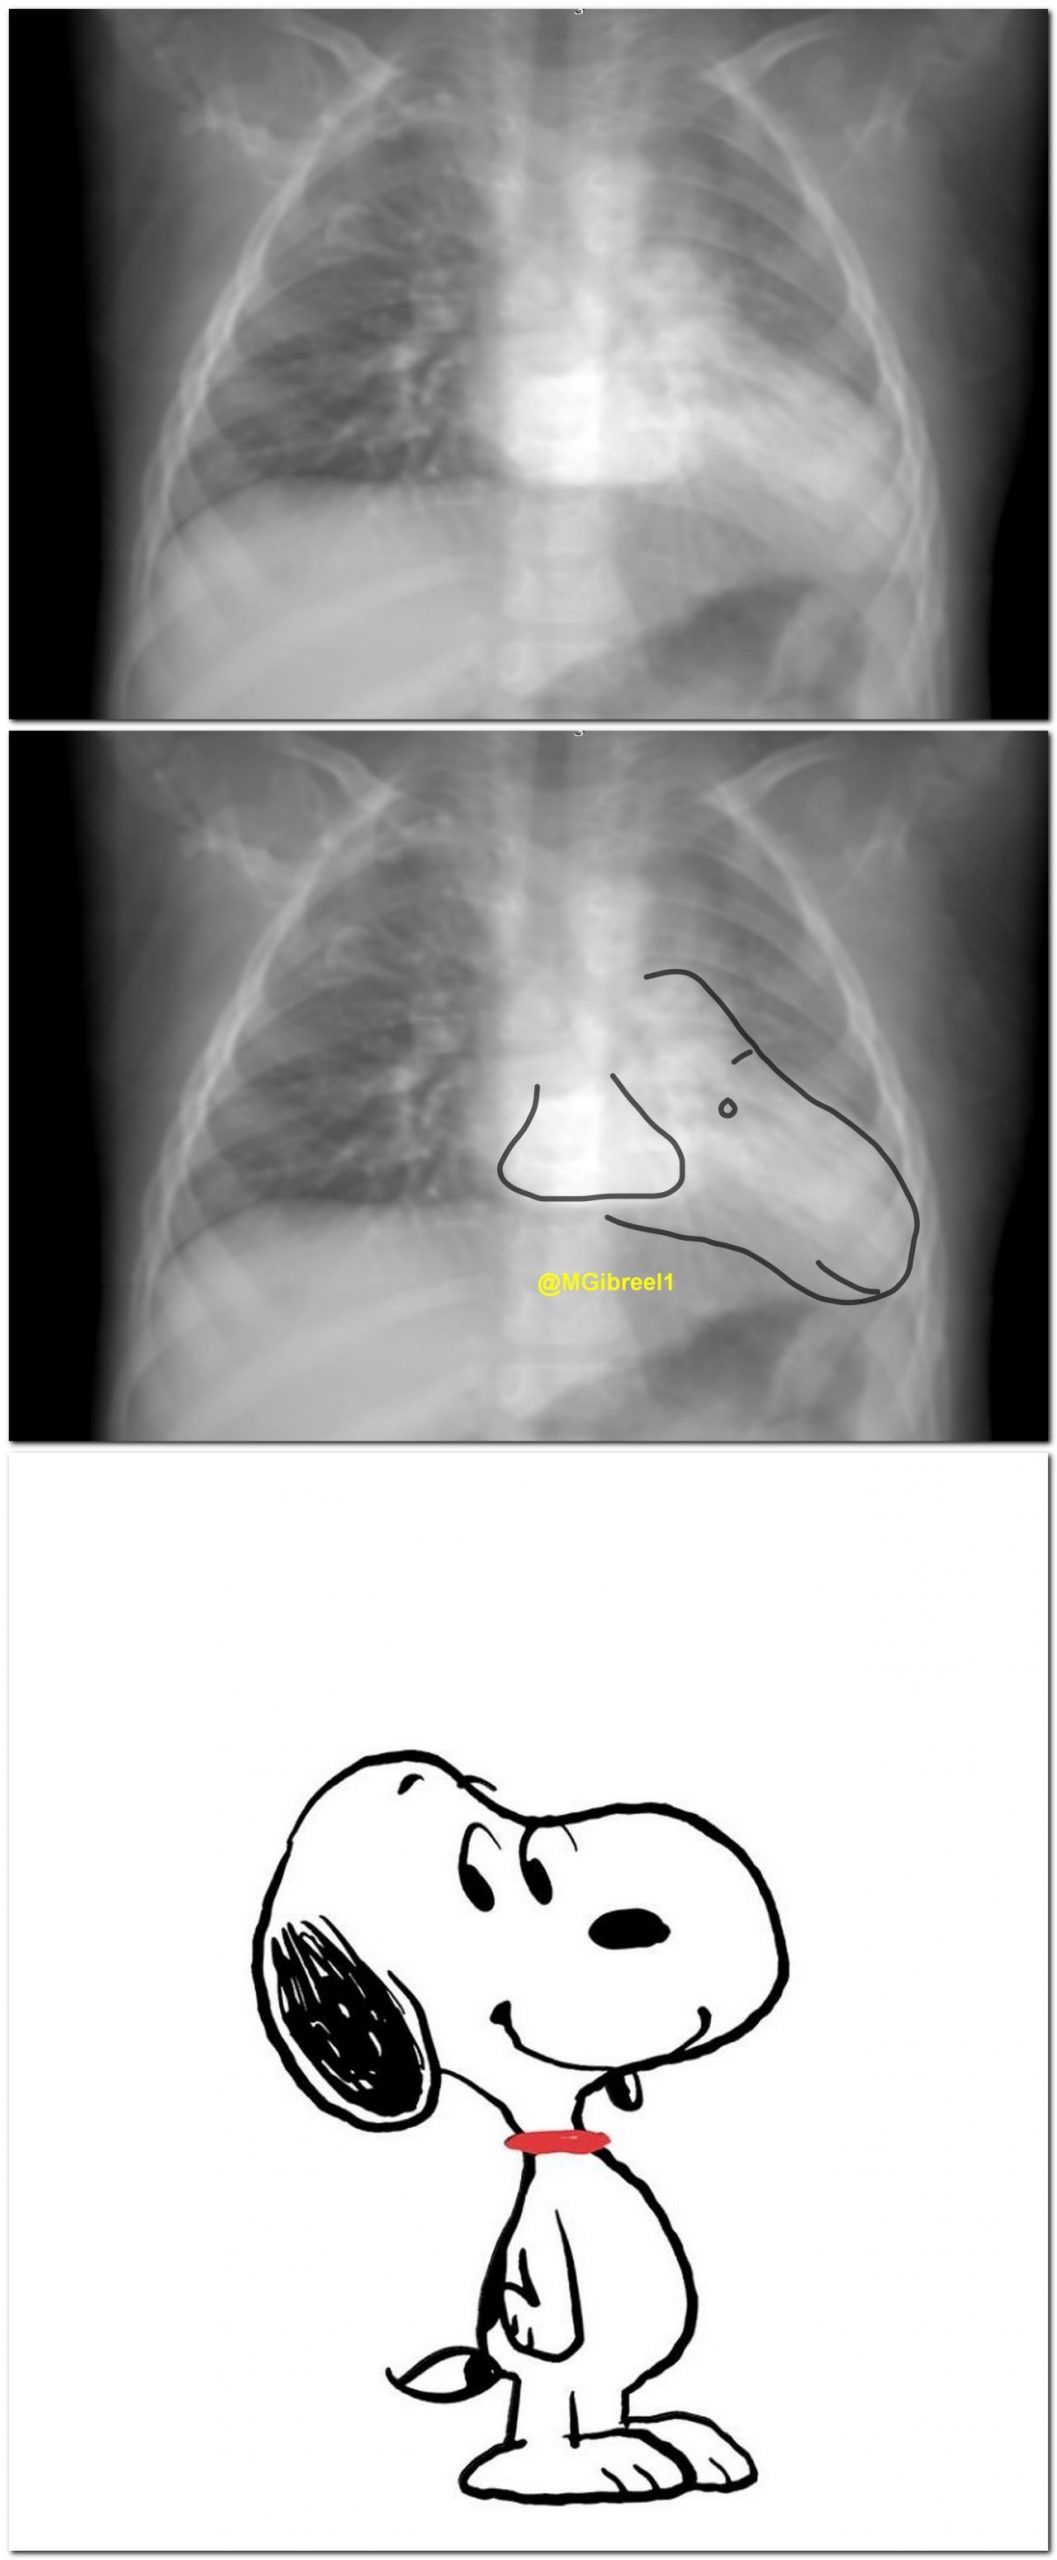

1 year TOF with pericardial agenesis

CT: signs of pericardial agenesis

1) Extreme levocardia.

2) Interposed lung between AO&PA.

Thick coronal-reformatted average (mean) projection (X-ray like) >>snoopy sign.